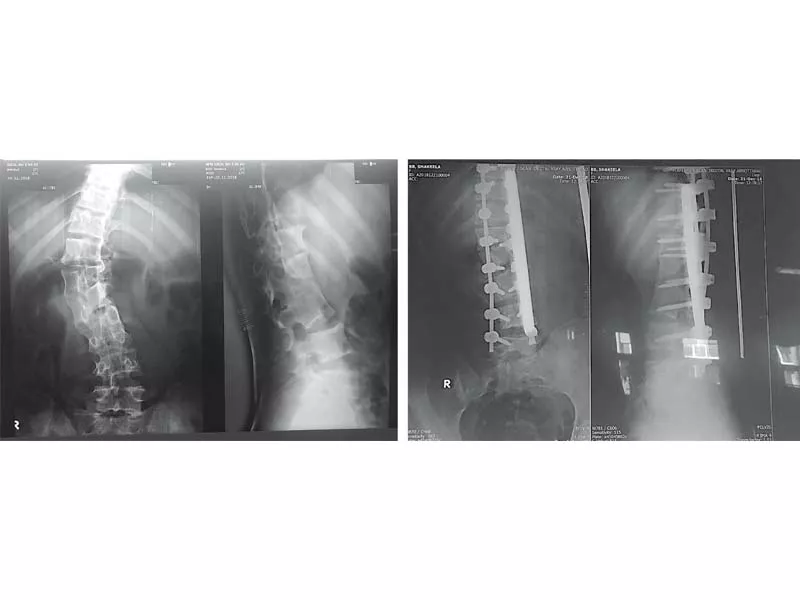

X-ray images of a patient before and after fixing of screws and rods in her spine at ATH. PHOTOS EXPRESS

Assistant Professor of Neurosurgery Dr Ehtisham said that the patient came to Neurosurgery OPD with deformity of back and severe a backache. “We put 18 screws of titanium in the bone around her spine during the eight-hour long surgery to correct the curvature using two rods of one foot each,” he said. The patient is completely stable and will be able to walk in two weeks. This surgery is very expensive outside, but here in our hospital it’s free of cost, he added.